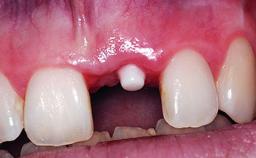

A 32-year-old female Caucasian patient with a compromised maxillary right central incisor was referred to us by a general dentist. Her chief complaints were discomfort and mobility of tooth 11 with unsatisfactory esthetics due to discoloration. The patient reported a previous trauma, some years earlier, as the origin of pathology on the afflicted tooth. Anamnesis was negative for any other dental or periodontal pathology in the remaining dentition. The patient did not take any medication and reported to be a light smoker (5–10 cigs/day). She had high esthetic expectations of her treatment. The extraoral examination revealed a high smile line with full exposure of her maxillary teeth and surrounding soft tissue in the area between the second premolars.

Case Type Single-Tooth Space

Jaw Maxilla

Area Anterior

# of Teeth 1

# of Implants 1